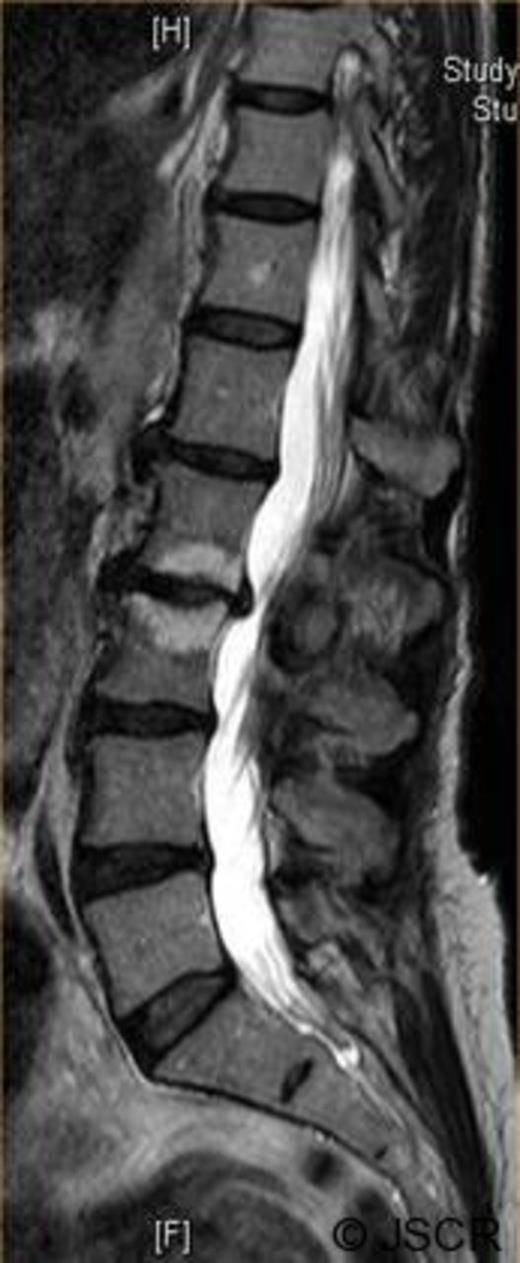

Magnetic Resonance Imaging scan (Fig. 1–4) showed L2/3 disc prolapse impinging on the right exit canal and causing L2 and L3 compression, thus she was listed for L2/3 lumbar discectomy and decompression. Examination of the right L2/L3 dermatomes revealed severe paresthesia and mild grade 4/5 weakness; reflexes were all normal. All other neurological examination was normal.

Preoperative axial T2 weighted image showing disc bulge at L2/3 to the right.